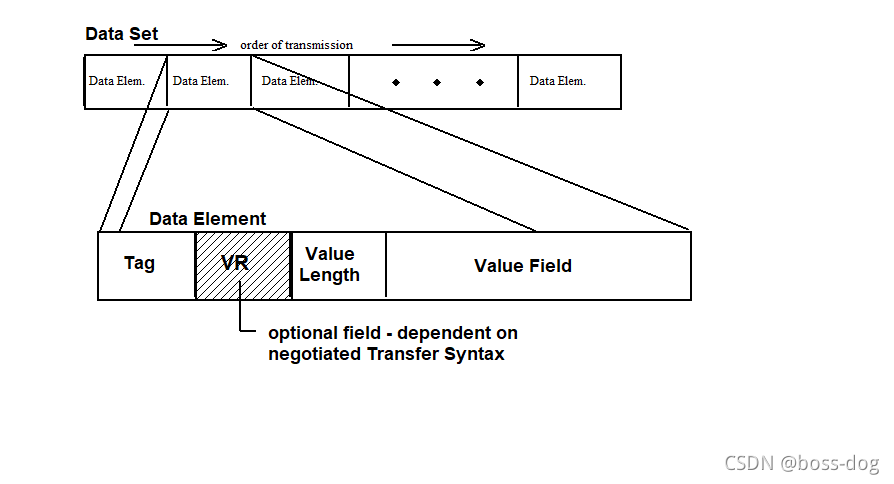

数据集(Data Set)和数据元素(Data Elements)

Tag(地址):譬如0020 0010地址

VR(可选项):可选字段依赖于协商的传输语法

Value Length(值长度):譬如名字给16位、字符给8位,根据值长度确定后面的Value Field(值域)

每一个信息都有一个标签(Tag),且是唯一的;

每个数据字段都有一个唯一的标记或键;

标签是是两个四位的16进制数来组成的,比如(7EF0 0010)就定义为tag标签。